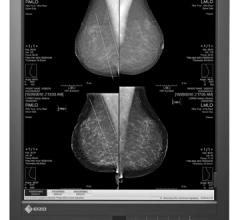

Sony now features diagnostic imaging displays for mammography as well as general imaging, such as: positron emission tomography/computed tomography (PET/CT), magnetic resonance imaging (MRI), X-ray nuclear medicine and ultrasound.

MRS (mammography reporting system) is a breast imaging tracking and reporting software that offers scalable solutions and integrations which can be tailored to fit a facility’s needs.